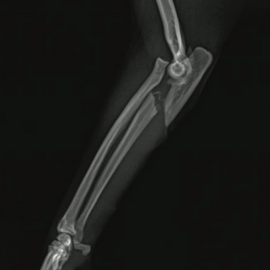

Fractura de Monteggia en paciente felino.